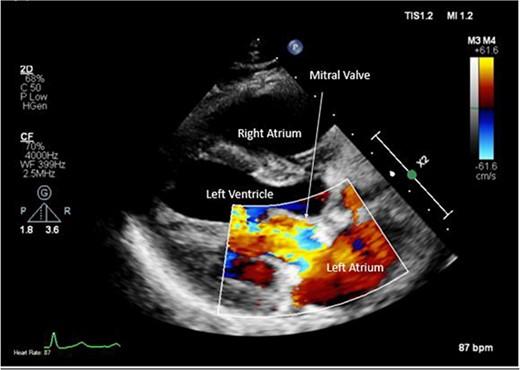

A CTPA was undertaken on Day 2, which excluded pulmonary embolism but confirmed bilateral peri-hilar consolidation and pleural effusions consistent with pneumonia. However, her pulmonary artery was dilated at 32 mm indicative of potential heart failure. On Day 5 of her ICU stay, a transthoracic echocardiogram was undertaken that revealed there to be severe mitral regurgitation including a mobile echogenic mass attached to the underside of the anterior mitral valve leaflet consistent with a vegetation (Figs 1 and 2).

Pre-operative TTE with Doppler depicting mitral valve with vegetation (labelled).